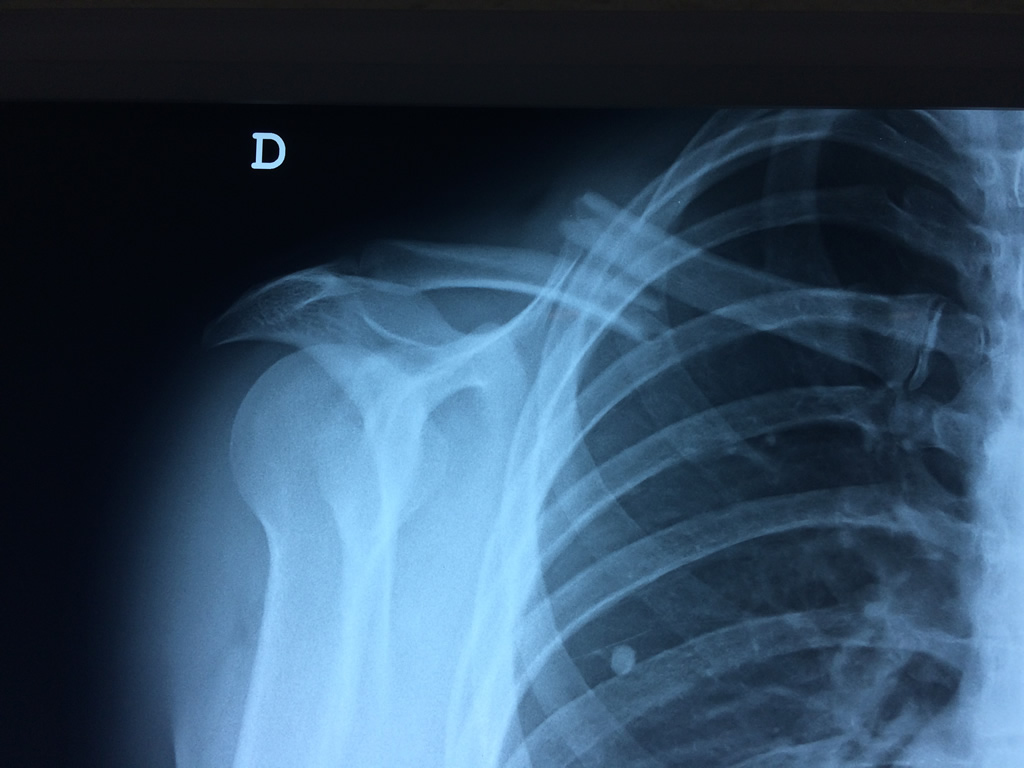

Clavícula

La clavícula es un hueso largo, con forma de "S" itálica, situado en la parte anterosuperior del tórax. Junto con la escápula forman la cintura escapular. Se puede palpar por toda su longitud y se extiende del esternón al acromion de la escápula, siguiendo una dirección oblicua lateral y posterior.